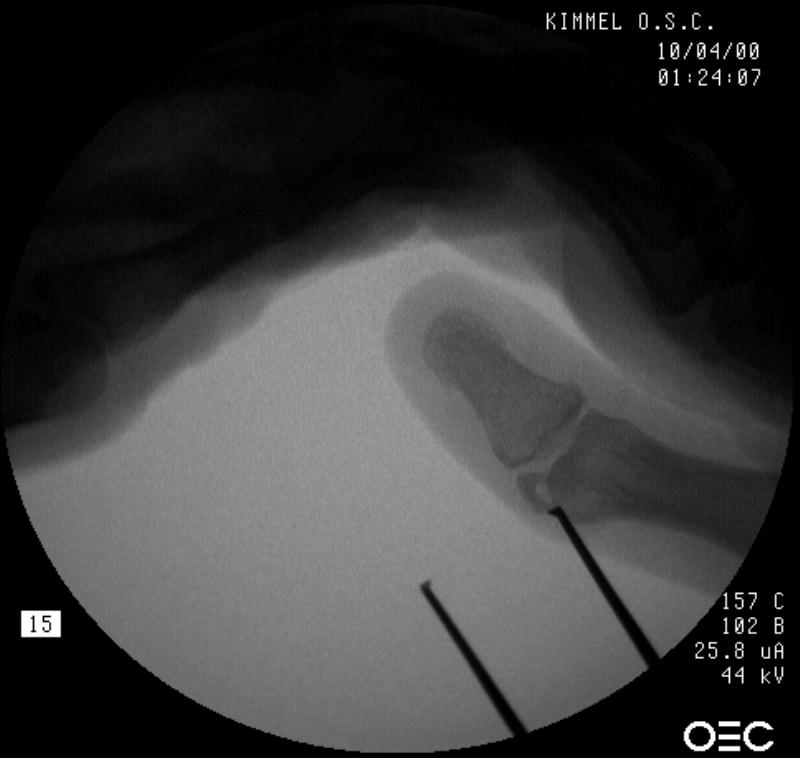

Intraoperative fluoroscopy. The mass:

Click for larger image

Osteotomy planning: proximal pin parallel to the proximal joint line, distal pin parallel to the distal joint line:

Pins were used as saw blade alignment guides:

Osteotomy closed:

Intraosseous wire passed through pin tracts, interfragmentary pin: